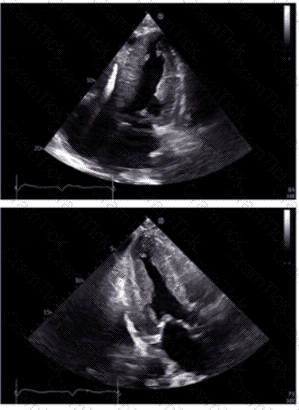

Which is the most likely abnormality represented in these images from a 48-year-old man with shortness of breath?